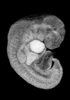

Carnegie Stage 14 (32 post-ovulatory days)

Most embryos at stage 14 are approximately 32 postovulatory days old and measure 5-7 mm in length. Distinguishing criteria for this stage include an open lens pit with invagination of the lens disc and elongated and tapering upper limb buds. The otic vesicle with a well-defined endolymphatic appendage is also a hallmark of this stage.